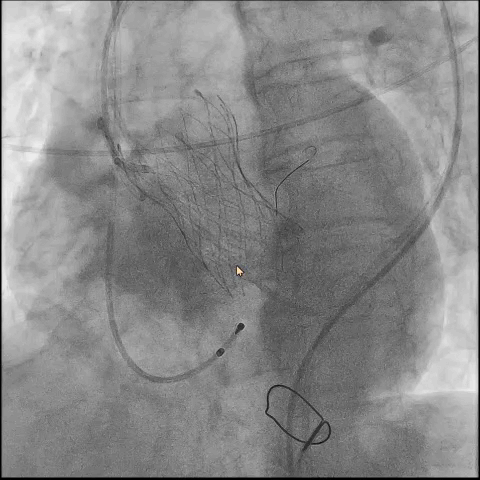

第三折:定位难

● 更换新瓣膜跨瓣后,猪尾难以送至无冠窦底,故行造影定位窦底。

隐约可见“无冠窦”后部更深窦底,位于“无冠窦”下约6mm,参考该位置后进行0位定位,无起搏逐步释放至工作位,瓣膜无明显位移表现,瓣膜形态压缩良好,造影评估无反流。准备释放瓣膜。

无张力释放,脱钩后瓣膜略微下滑,约位移瓣环下4~5mm位置,瓣膜整体形态良好,造影评估无可见反流。

超声评估,微量瓣周反流,二尖瓣工作良好,植入位置理想。

结束手术,一波三折终成功!